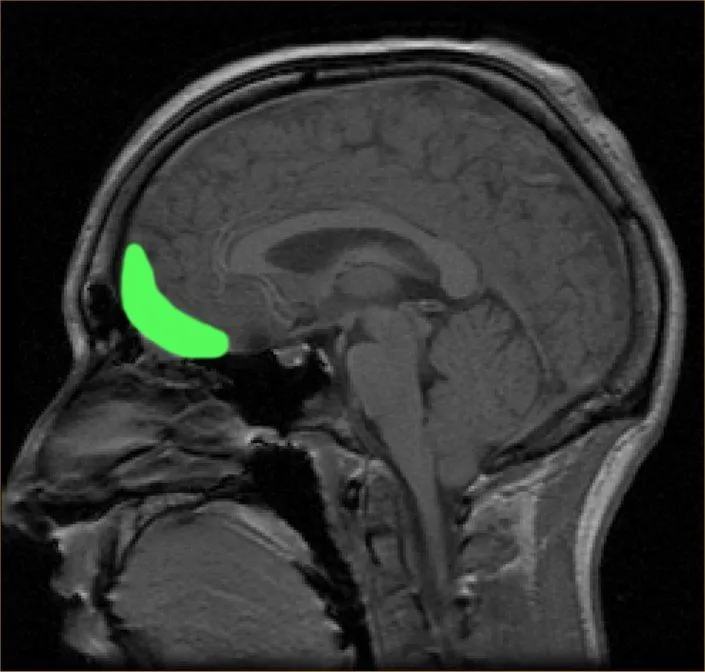

Speaking from a physiological perspective, dance’s music is known to stimulate the orbitofrontal cortex of the brain, which is located right behind the eyes. The orbitofrontal cortex is the major reward and pleasure region of the brain. The amount of stimulation caused here is dependent on how much we enjoy a particular tune.